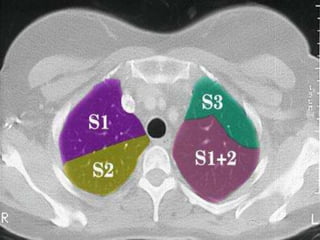

CAÂY PHEÁ QUAÛN VAØ PHAÂN

THUØY PHOÅI

+CT cho chi tieát giaûi phaãu toát raát nhieàu so

vôùi X quang qui öôùc

+Phaân tích hình aûnh CT

-Caây pheá quaûn

-Phaân thuøy phoåi

-Raõnh maøng phoåi